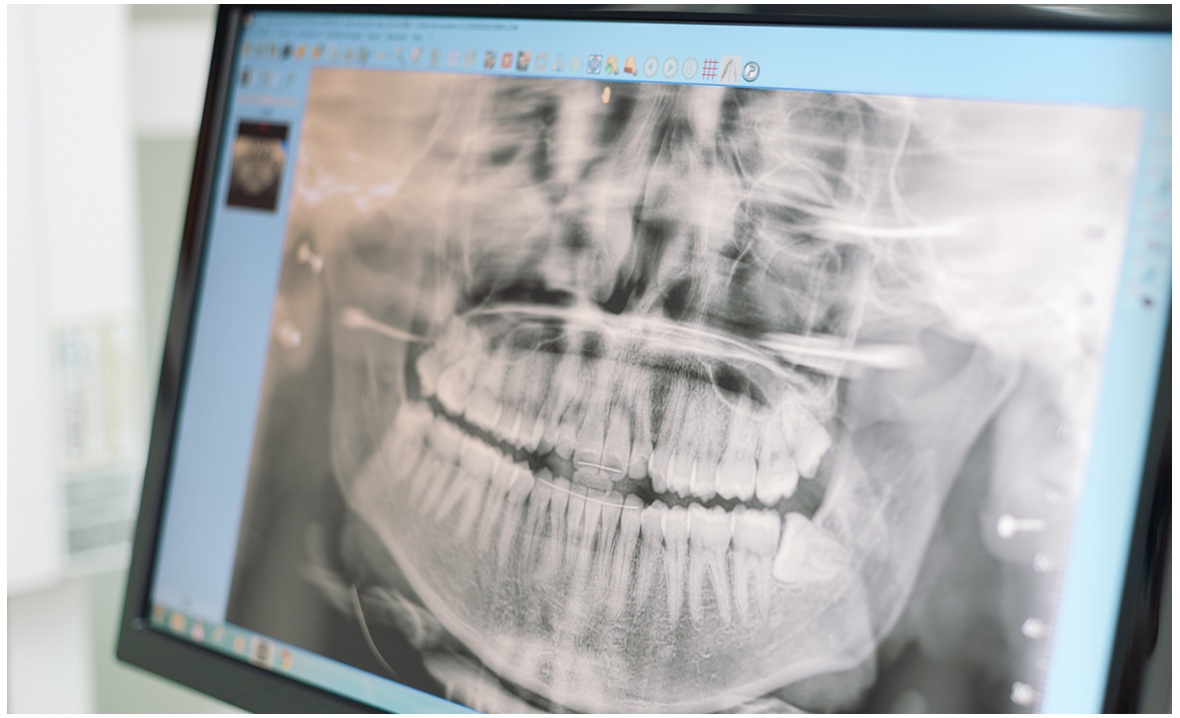

Un esame che consente di ottenere informazioni sulla muscolatura masticatoria è l’elettromiografia dentale. Quest’ultima consente di fare delle indagini diagnostiche dell’ATM (Articolazione Temporo Mandibolare). Si tratta di un’articolazione doppia, la cui conformazione consente di garantire un movimento di rotazione con la parte superiore, e di traslazione con la parte inferiore.

Questo movimento complesso è garantito da un preciso equilibrio tra strutture dentali, articolari e muscolari. Ma mentre la dentatura può essere controllata in maniera diretta, e le strutture scheletriche tramite indagini radiologiche, fino a qualche tempo fa non vi erano dei modi diretti di indagare la muscolatura masticatoria.